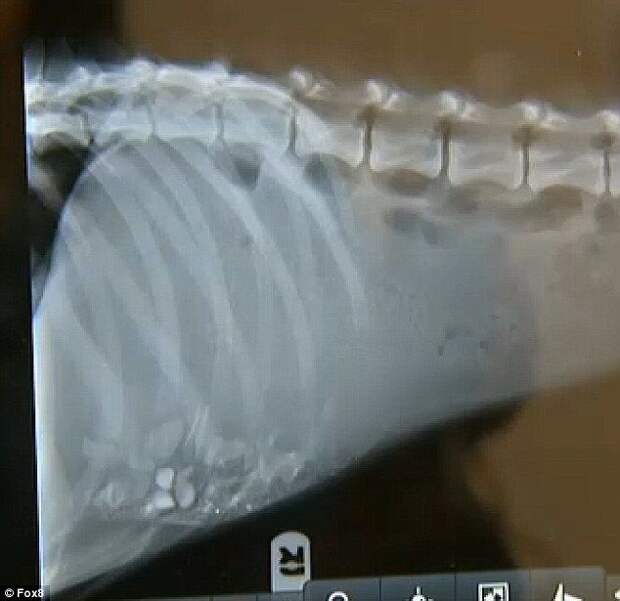

Волонтёры сделали Алексу рентген и обнаружили в его желудке ветки и камни, которые он ел, чтобы не умереть с голоду.